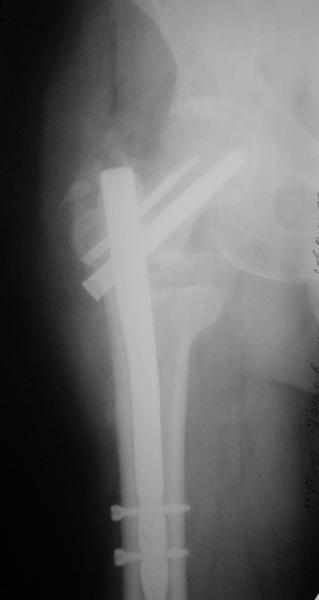

Гвоздем тоже можно, но технически труднее, надо вводить джойстики в шейку...

В приложении пример с гвоздем.